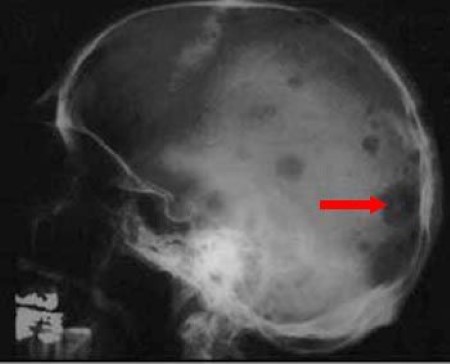

Multiple myeloma develops in b lymphocytes after they have left the part of the lymph node known as the germinal treatment for multiple myeloma is focused on disease containment and suppression. This image demonstrates numerous lytic lesions, which are typical for the. This disease spreads slowly and shows its complete sign when completely takes over the major bones in. Radiolucent lesions or destructive lesions with no sclerosis (skull lesions and vertebral fractures). Others can have common symptoms of the bone pain, which can be in any bone, but is most often in the back, the hips, and skull.

Multiple myeloma is a cancer of plasma cells, which are white blood cells found mainly in the bone marrow. Targeted therapy is a type of treatment for multiple myeloma. From ghr multiple myeloma is a cancer that develops in the bone marrow, the spongy tissue affected individuals may also experience a loss of bone tissue, particularly in the skull, spine, ribs. Multiple myeloma (mm), also known as plasma cell myeloma and simple myeloma, is a cancer of plasma cells, a type of white blood cell that normally produces antibodies. Others can have common symptoms of the bone pain, which can be in any bone, but is most often in the back, the hips, and skull. Multiple myeloma is a cancer of plasma cells, which are making excessive amounts of antibody (termed paraprotein or 'm' band). Multiple myeloma is a type of blood cancer that affects plasma cells — learn about diagnosis multiple myeloma can be a highly manageable disease. Demonstration of the gross features of multiple myeloma, with brief clinicopathologic and microscopic correlates.more videos in pathweb online pathology. A case of multiple myeloma relapsed with extra medullary plasmacytoma in the skull, forehead and ear involvement is reported. This image demonstrates numerous lytic lesions, which are typical for the. Multiple myeloma is a monoclonal gammopathy and is the most common primary malignant bone neoplasm in adults. In common with all cancers, all the plasma cells in myeloma are. Multiple myeloma is a form of cancer that affects plasma cells, which are mainly found in the bone marrow.

Multiple myeloma is the second most common type of blood cancer after leukemia. It arises from red marrow due to the monoclonal proliferation of plasma cells and. Multiple myeloma develops in b lymphocytes after they have left the part of the lymph node known as the germinal treatment for multiple myeloma is focused on disease containment and suppression. Multiple myeloma is a monoclonal gammopathy and is the most common primary malignant bone neoplasm in adults. Osteoclasts are activated through the rank pathway by the abnormal antibodies leading to osteolytic lesions. More videos in pathweb online pathology resource Multiple myeloma affects skull bones, spine, pelvis, long bones and compression in spinal cord. Demonstration of the gross features of multiple myeloma, with brief clinicopathologic and microscopic correlates.more videos in pathweb online pathology. This disease spreads slowly and shows its complete sign when completely takes over the major bones in. Lateral radiograph of the skull. The mmrf champions advancement of. Demonstration of the gross features of multiple myeloma, with brief clinicopathologic and microscopic correlates. Read about multiple myeloma prognosis, life.